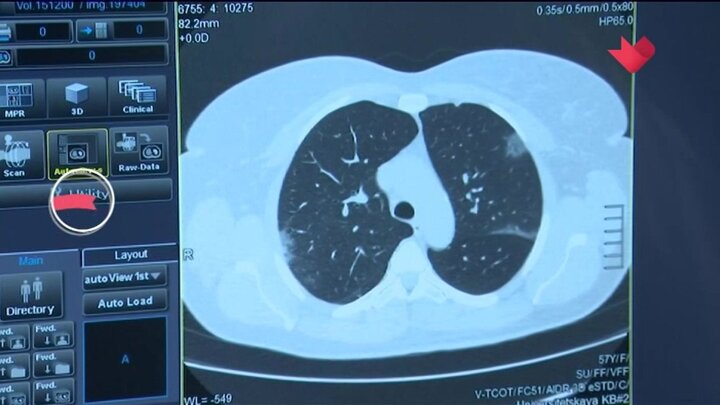

Более 10 тысяч раз российские врачи воспользовались КТ-калькулятором для диагностики COVID-19. Система разработана в Москве специалистами больницы имени Ворохобова и МГУ.

Состояние легких пациента определяют по анализу крови, ее насыщенности кислородом и по общей клинической картине. После обработки полученных данных КТ-калькулятор прогнозирует вероятность легкого, среднего или тяжелого течения пневмонии.